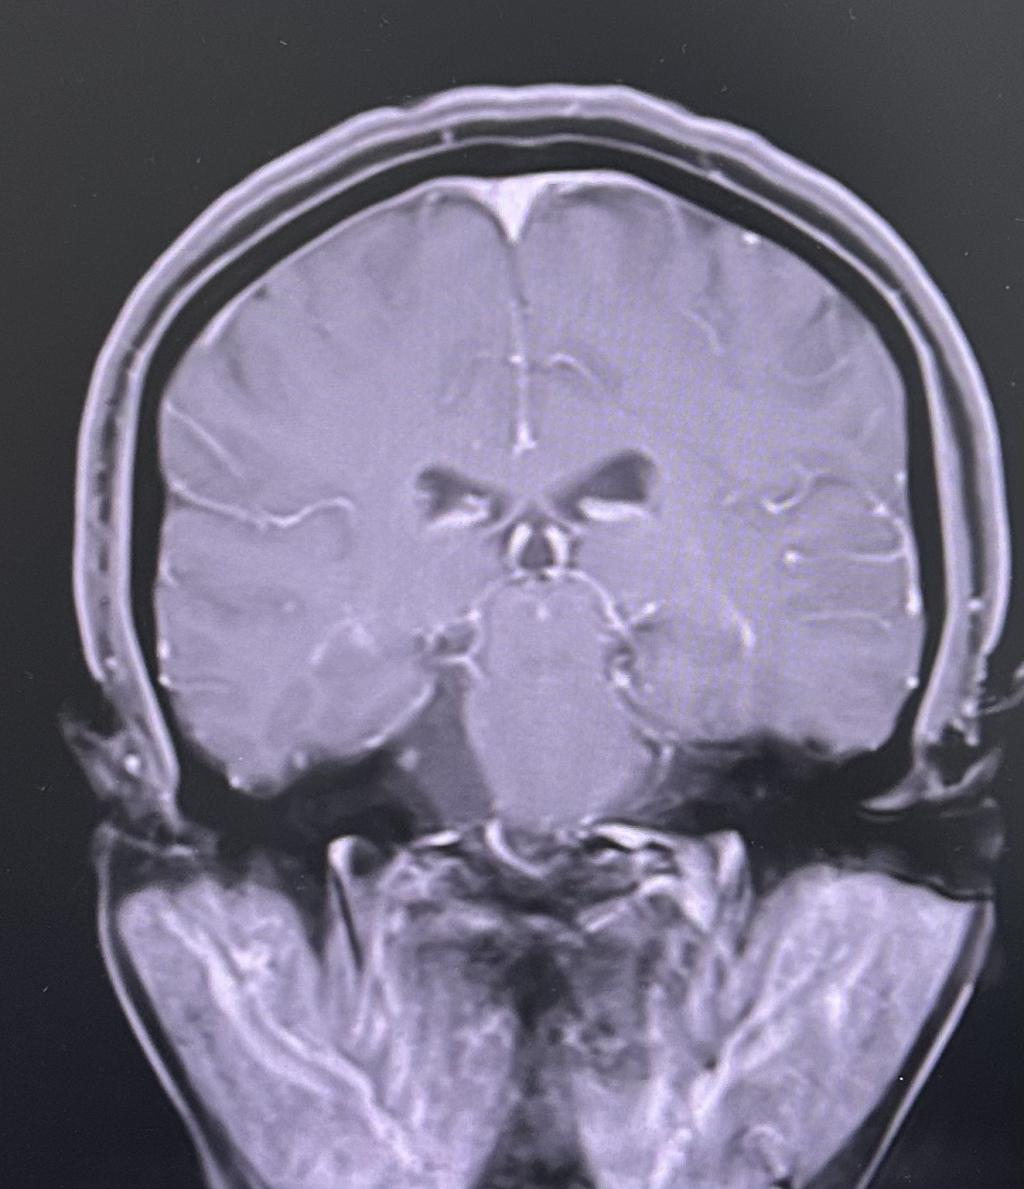

为求进一步治疗,贾女士慕名来到我院门诊就诊。门诊行颅神经-平扫(MR)提示:右侧桥小脑角区占位性病变,收治入神经外科住院治疗。

患者术前核磁共振影像